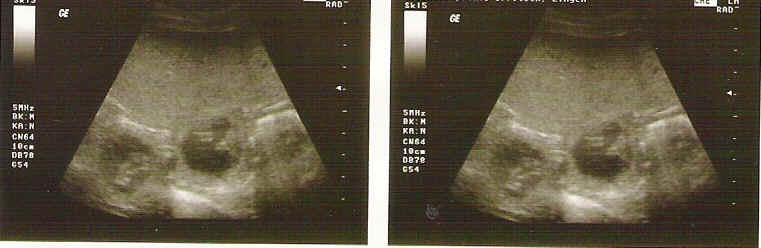

Brisby van Noort Ultraschallbilder " D - Wurf "

Vater: Broncor v. Speichersee Mutter: Brisby van Noort

Ultraschallbilder der Hündin Brisby van Noort, erstellt am 28. Tag.